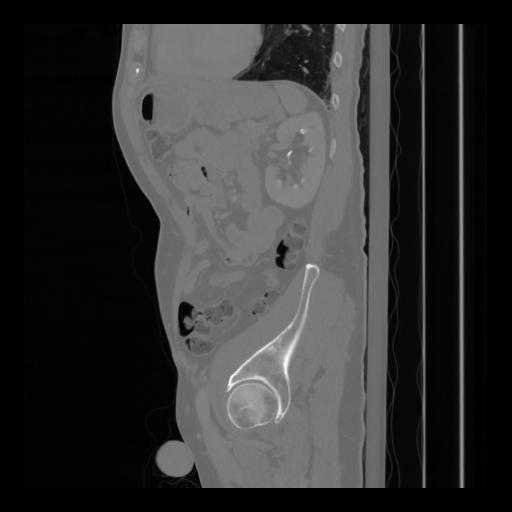

36 CUERPO,CE,Sagittal,3.000,CUERPO,Sagittal,